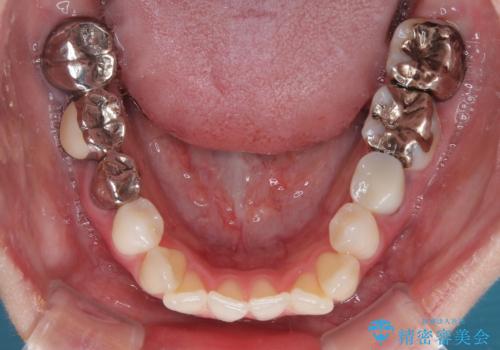

- 上下前歯のデコボコとクロスバイトを気にして来院された患者様です。

治療済みの処置歯が多いため、インビザラインを用いて矯正治療を行うこととしました。

下顎臼歯部にブリッジが装着されており、移動不可のため、IPR(歯と歯の間を削る)と歯列全体を拡大させることで、歯並びを整えていくこととしました。

インビザライン特有の奥歯の噛みにくさが治療後半に発現しましたが、無事に終了させることができました。